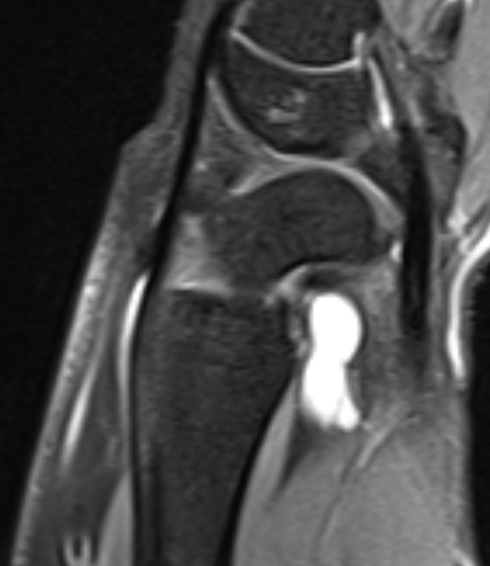

Dorsal ganglion

Dorsal ganglion arising from scapholunate joint

Dorsal ganglion arising from scapho-lunate joint